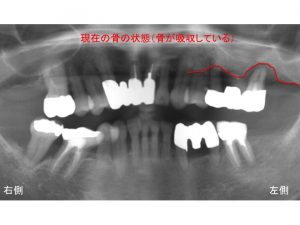

早速レントゲン写真からみましょう!

上顎左側の奥歯がグラグラするため

抜歯し、インプラント治療を行ったケースです。

歯を支えている骨が吸収しています。

現在の骨の状態を赤線で表示します。